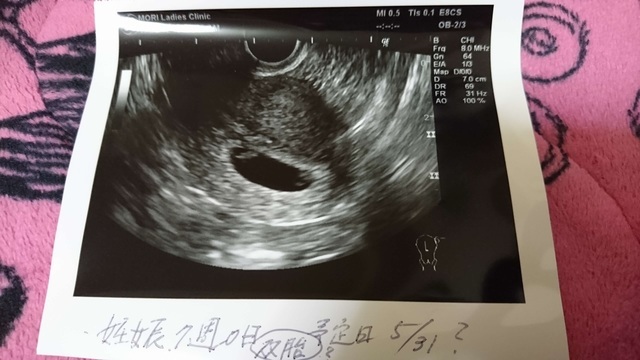

7週0日(7w0d・男の子)|るちゃんHA さん(22歳)

エコー写真撮影時のエピソード:月経がこず、ストレスできてないだけかと思いきや、妊娠検査薬を使用したら陽性反応が出たのでその翌日に病院に行き、内診してもらったところ、卵が2つあるよと言われ、双子だと思う。と言われてとてもびっくりしました。その日にちゃんと心音も聞けました。